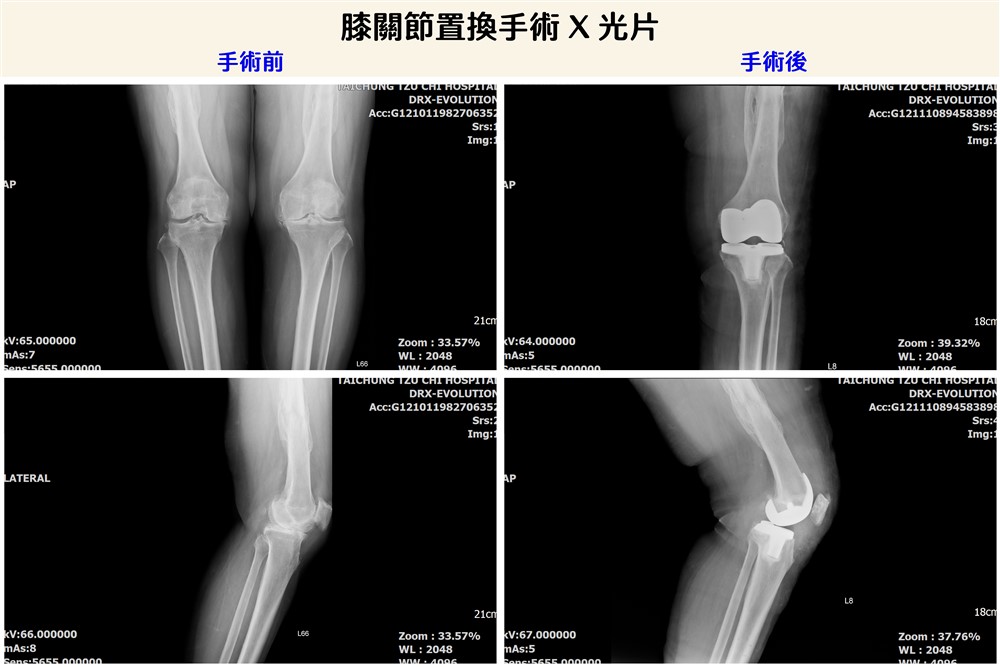

陳女士接受膝關節置換手術前後X 光檢查影像。